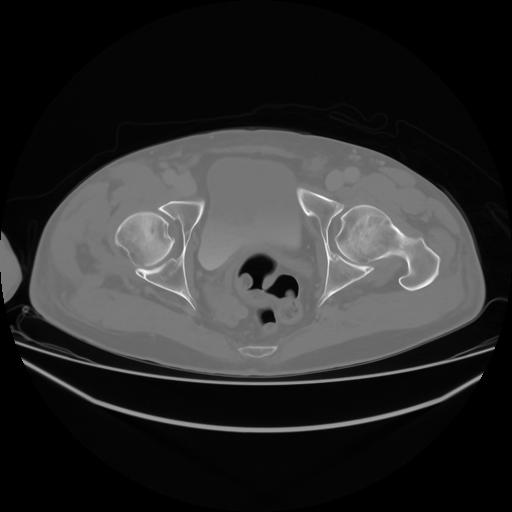

4 CUERPO,CE,Axial,3.0,CUERPO,,